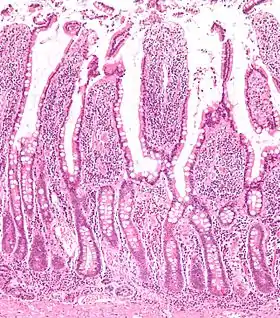

![]() صورة مجهرية of the أمعاء دقيقة غشاء مخاطي showing intestinal villi - top half of image.[1][1] صبغة الهيماتوكسيلين واليوزين | |

صورة مجهرية للزغابات المعوية. Section of duodenum of cat. X 60